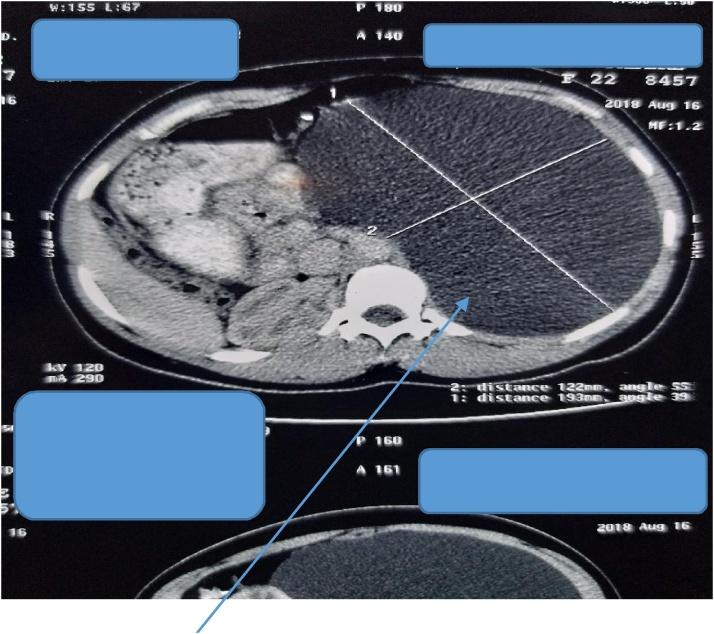

Two female patients aged 22 years and 65 years respectively, and an 11-year-old boy presented with giant pancreatic pseudocysts (>10 cm in diameter each) to our unit and were successfully managed. They all underwent exploratory laparotomy and cysto-gastrostomy with good outcome.

两名分别为22岁和65岁的女性患者以及一名11岁男孩因胰腺巨大假性囊肿(直径均>10 cm)前来我院就诊,并成功接受治疗。他们均接受了剖腹探查术和囊肿胃吻合术,效果良好。